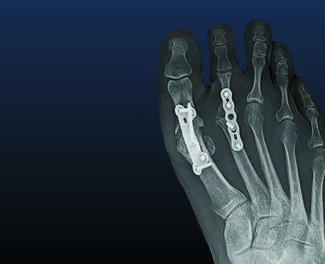

Kristen M. Brett, DPM; Kyle W. Abben, DPM, FACFAS

The impact of pain and joint degeneration in the second metatarsophalangeal joint (MPJ) is far reaching throughout the foot and ankle. Here the authors outline crucial surgical intervention pathways to address such pathology, to guide...

The impact of pain and joint...